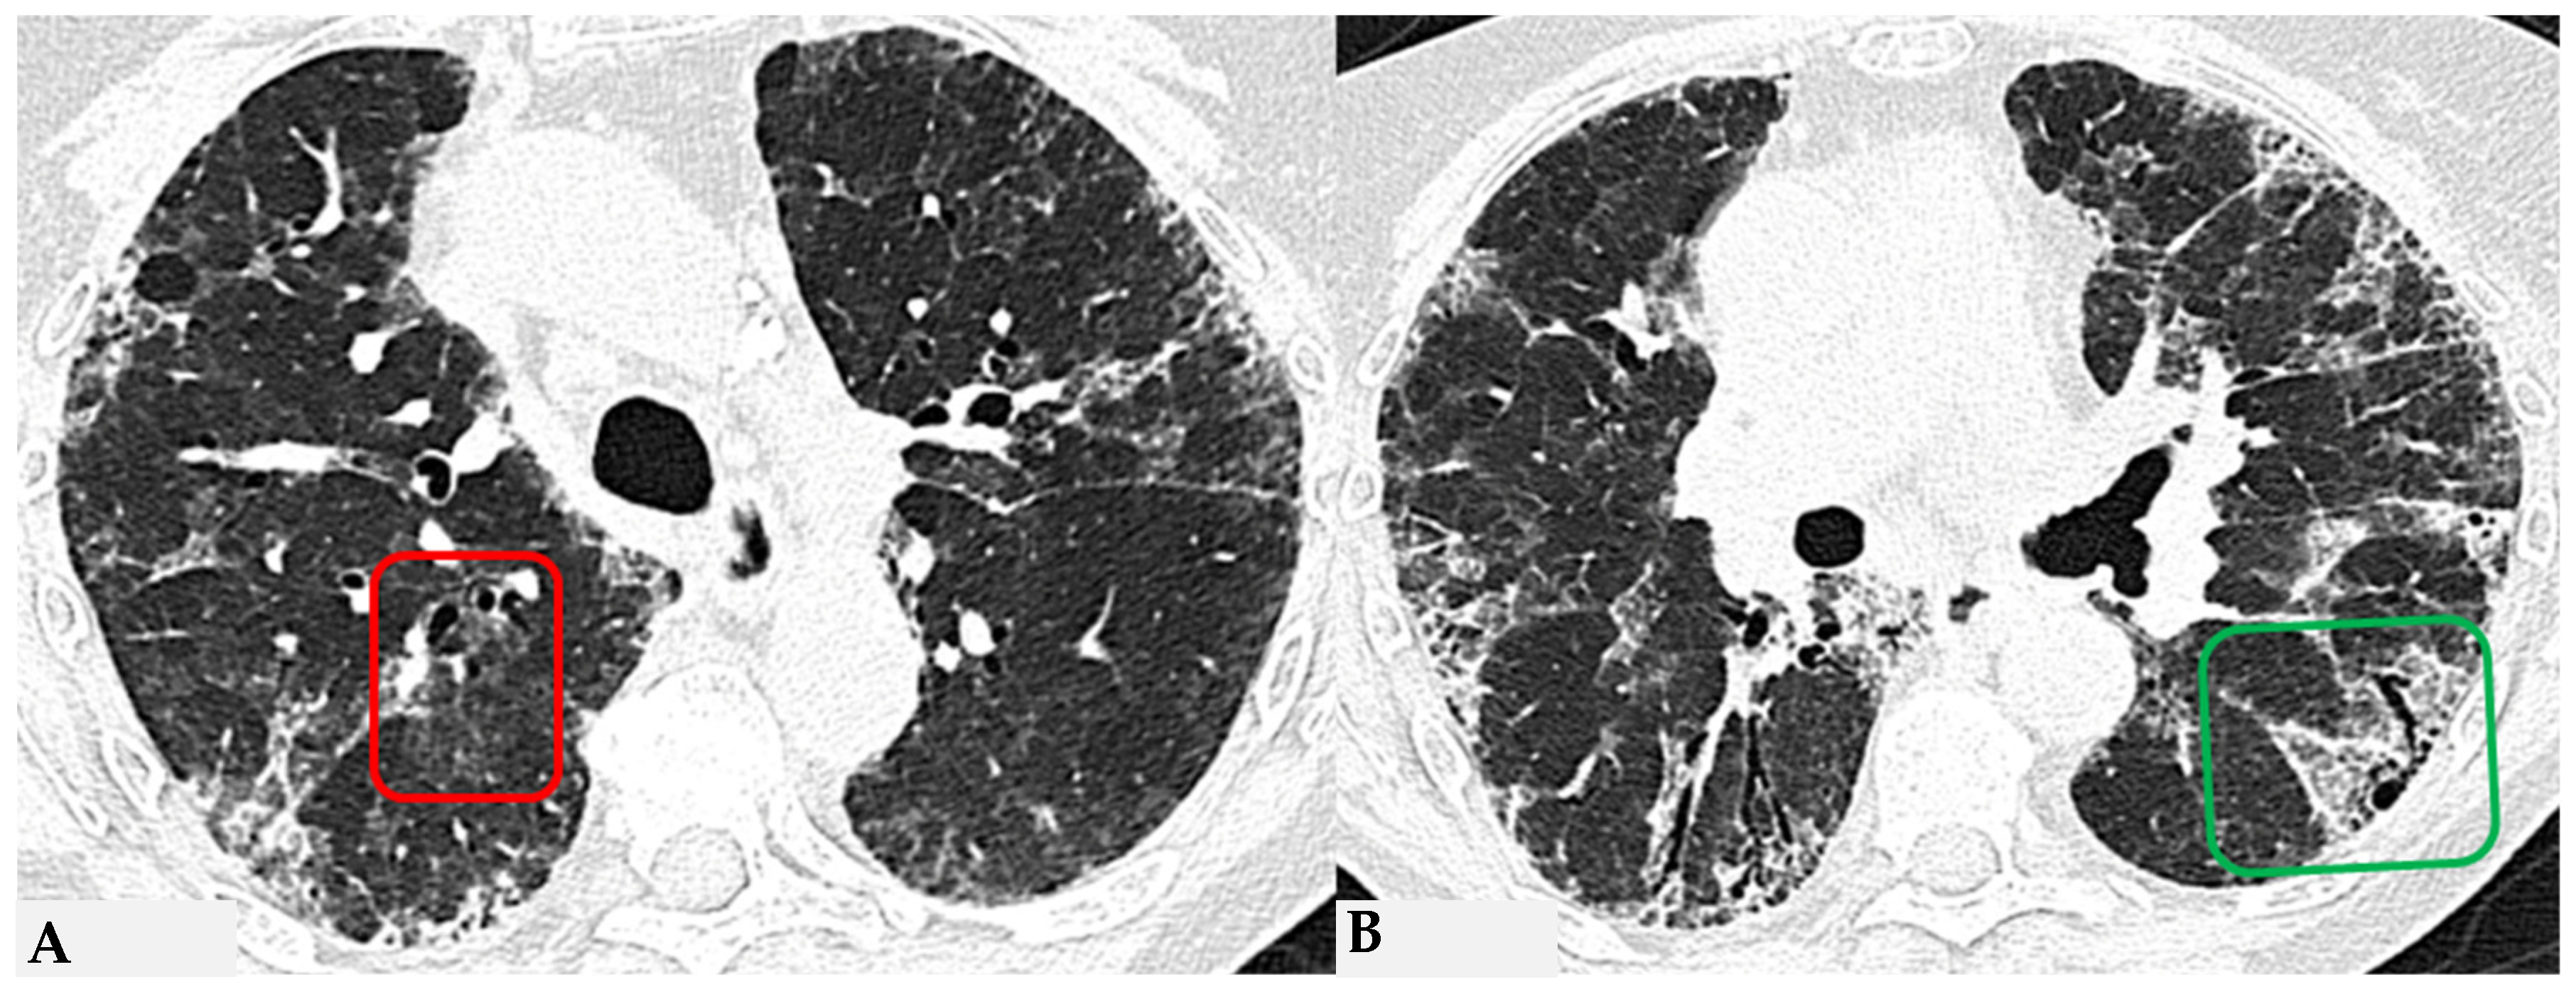

HRCT of the chest and magnification areas of RLL and LUL in FHP. Three-density pattern with lobular areas of reduced attenuation in both lungs (magnification images), overlapping with areas of increased density where distinct fibrotic alterations are evident, characterized by intra- and inter-lobular thickening with traction bronchiectasis and bronchiolectasis (red box). In certain patients, the absence of typical HRCT fibrotic features leads to their classification as “pattern compatible with FHP”. Suggestive elements of this pattern are fibrosis with a mixed central and peripheral distribution (Figure 7) and the fibrotic pattern with basal predominance (Figure 8).

Figure 7.

FHP with small areas of GGO related to acute exacerbation: axial chest HRCT scan. HRCT pattern characterized by mild amorphous GGO components in the upper lobes (red box), predominantly centrally located, with sectoral signs of interface and anterior asymmetric reticulations. Minimal traction bronchiolectasis coexists (A); subcarinal scan reveals GGO with moderate distortion, septal thickening and alterations predominantly bronchocentric in distribution (green box in (B)). The changes exhibit a “patchy” distribution with areas of mosaic attenuation.